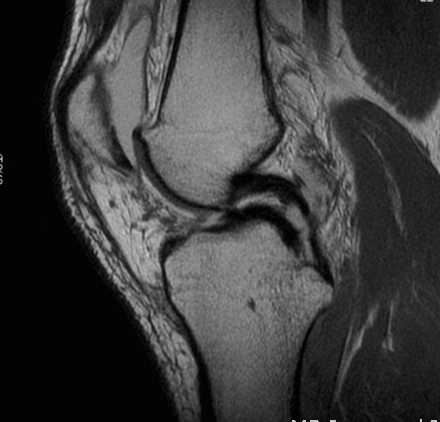

Signs of bucket handle tear meniscus

1. Double PCL sign

- medial Meniscus

2. Absent bow tie sign

- should see bow tie image on 2 consecutive sagittal slices of 5 mm

3. Fragment in notch sign

4. Anterior flipped meniscal sign

- torn fragment flips over the anterior horn of the affected meniscus

5. Truncated meniscus